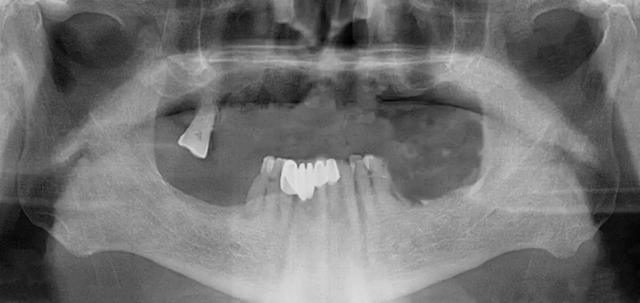

家住安丘的郎先生,因上牙床僅剩一顆牙齒,吃飯很受影響。在了解到濰坊市中醫(yī)院口腔科種植全口牙當(dāng)天可以接著戴牙吃飯,慕名來找李德仁主任尋求幫助。

口腔科李德仁主任為老人仔細(xì)檢查了口腔情況,由于缺牙時(shí)間太久,牙床骨量極少,正常的種植修復(fù)需要植骨,手術(shù)創(chuàng)傷大而且半年后才能鑲牙吃飯。建議他進(jìn)行數(shù)字化導(dǎo)板種植,可以不用植骨而且當(dāng)天就能戴牙吃飯,手術(shù)簡(jiǎn)單,創(chuàng)傷小。老人和孩子很信任的接受了李主任的種植方案:上牙床種植5顆,下牙床種植4顆,當(dāng)天戴牙吃飯。